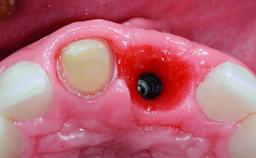

A 32-year-old female Caucasian patient with a compromised maxillary right central incisor was referred to us by a general dentist. Her chief complaints were discomfort and mobility of tooth 11 with unsatisfactory esthetics due to discoloration. The patient reported a previous trauma, some years earlier, as the origin of pathology on the afflicted tooth. Anamnesis was negative for any other dental or periodontal pathology in the remaining dentition. The patient did not take any medication and reported to be a light smoker (5–10 cigs/day). She had high esthetic expectations of her treatment. The extraoral examination revealed a high smile line with full exposure of her maxillary teeth and surrounding soft tissue in the area between the second premolars.

# of Implants | 1 |